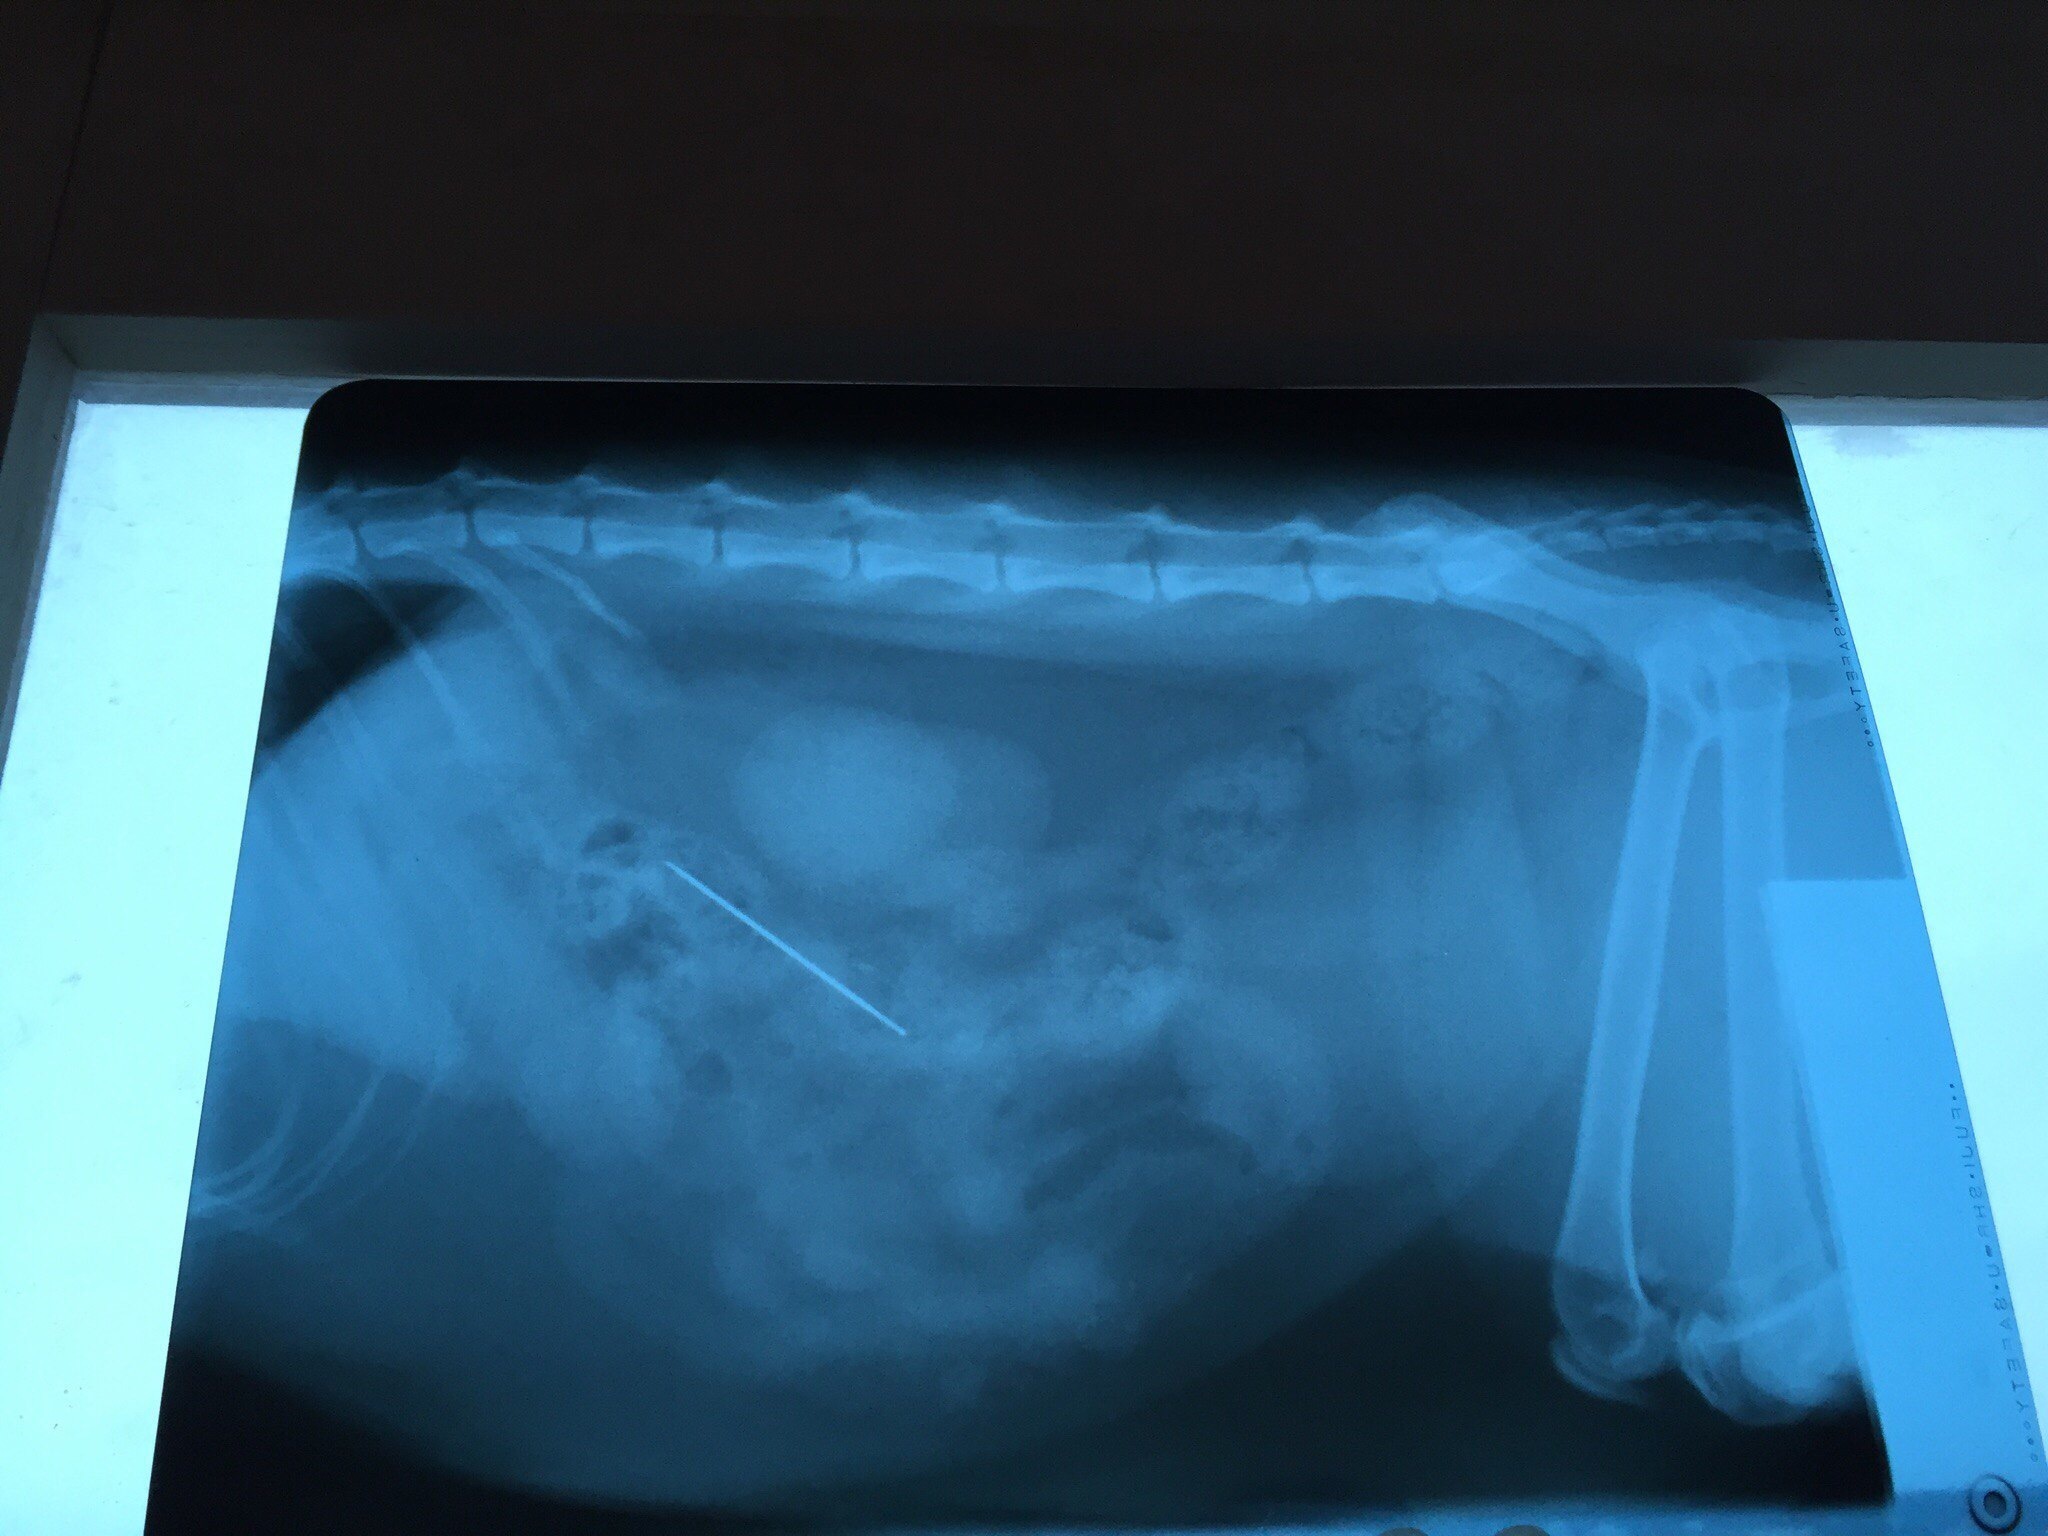

Вот как-то так выглядит кот напросвет. Теплоты там особо не видно, зато есть целый комплект косточек и перелом четвертой пястной кости.

Пока люди отвернулись, Линукс порвал сетку, вышел погулять на карниз и превратился в ракету класса "окно-асфальт". Жив, цел, орёл, месяц ходил со спицей в лапе, и всё равно умудрялся буянить по ночам.